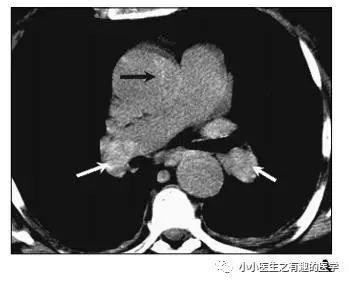

如图,高密度影的那一条。

不怕,有增强CT证实。

是不是很有趣。

再来一个图。

仔细看,有端倪。

增强CT可以核实。

很明显,患者做了CT平扫,我们要仔细阅片,发现可疑,及时增强CT,要不然就漏诊了。